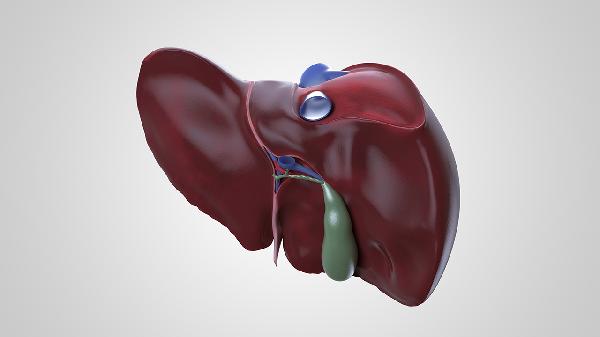

肝脾肿大可致腹部轮廓异常,叩诊呈浊音。腹水形成时可见脐部突出或移动性浊音,腹围短期内增加超过2厘米需重视。先天性肝纤维化、糖原累积症等遗传代谢病常伴此体征。

发现上述症状建议完善肝功能检测ALT/AST值、凝血功能筛查及腹部超声。日常需保证足够热量摄入,选择中链脂肪酸配方奶粉更易吸收。避免使用对乙酰氨基酚等肝毒性药物,接种甲肝、乙肝疫苗可预防病毒性肝炎。母乳喂养母亲应戒酒并慎用中药制剂,定期监测宝宝生长发育曲线有助于早期发现异常。